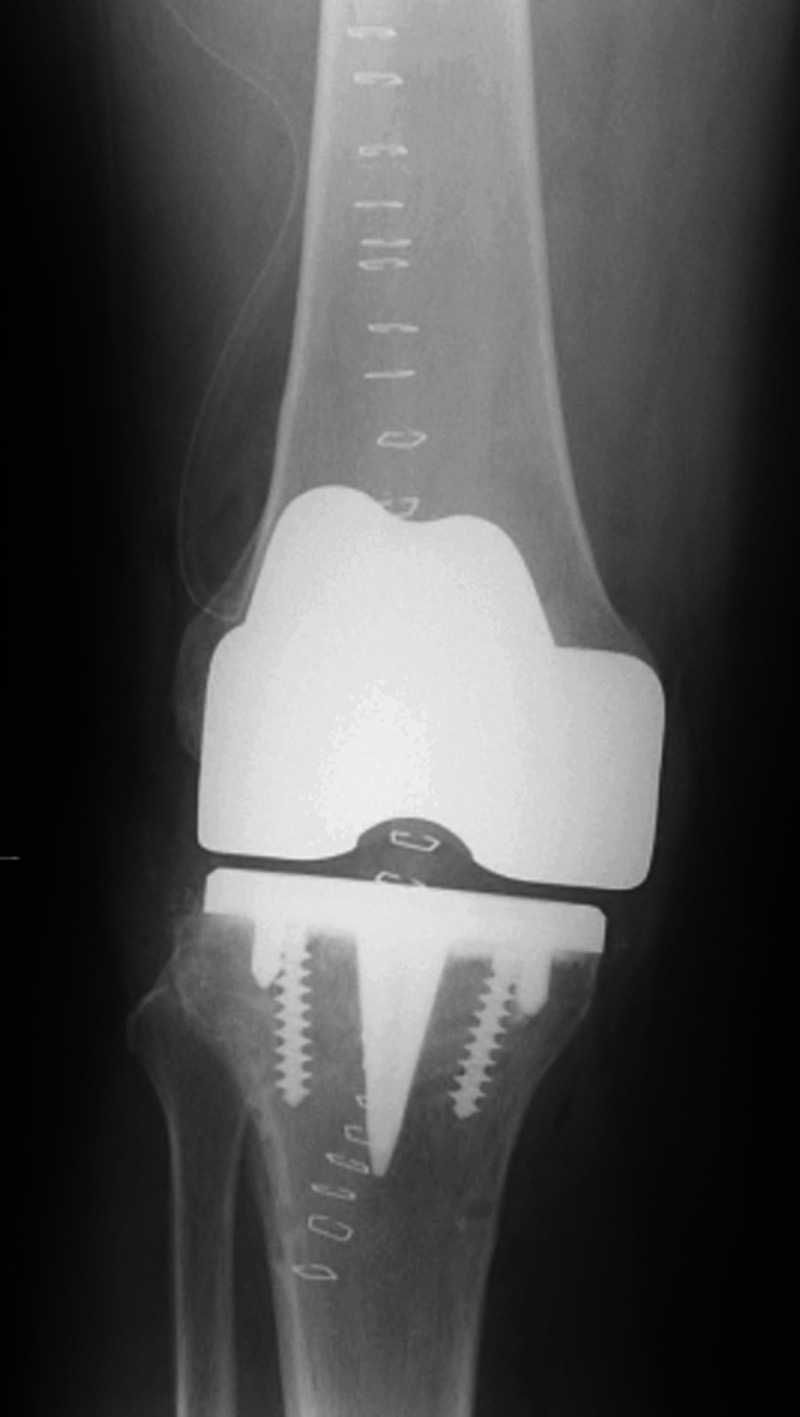

Left knee cruciate substituting revision knee arthroplasty Left knee cruciate substituting revision total knee arthroplasty Cruciate substituting knee prosthesis - AP view Cruciate substituting knee prosthesis - latera view

46 year-old man with knee revision arthroplasty   Note the large distal femoral box. There is a surgical drain in the suprapatellar space. From Taljanovic, 2005